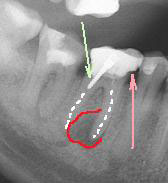

На этом рентгеновском снимке видны, в первую очередь, «пустые» корневые каналы и довольно больших размеров очаг воспаления (то, что часто называют гранулемой, кистой) на верхушке одного из корней. В общем итоге в одном зубе был сконцентрирован целый букет ошибок и недоделок, одним словом, это образец недобросовестной работы стоматолога. Я стараюсь о коллегах всегда говорить или хорошо или молчать, но в данном случае надо смотреть правде в глаза – зуб загублен именно стоматологом. Никаких объективных сложностей для качественной работы изначально здесь не было. Зато появились теперь. Прогноз на будущее для таких зубов всегда строится, исходя из 2 основных проблем – насколько приведет к успеху повторное лечение каналов и насколько будет успешной попытка адекватного восстановления зуба после этого. Оценив вероятность долговременного успеха этих двух составляющих, можно решать, стоит ли «спасать» зуб от щипцов хирурга. Ведь, в любом случае, лечение стоит денег, а гарантировать результат здесь невозможно. Можно только предполагать вероятность успеха. В данном случае каналы не выглядели непроходимыми. Да и восстановить зуб коронкой, даже несмотря на большую степень разрушения, все еще представлялось возможным. А потому было принято решение о начале лечения.

Что касается корневых каналов, то именно здесь и были основные сложности. Оба канала были не слишком здорово обработаны и запломбированы, в результате чего на обоих корнях появились гранулемы.

Но обычный рентгеновский снимок дает плоское 2хмерное изображение, разные структуры накладываются друг на друга, и сложную анатомию каналов на нем не всегда можно разглядеть. Что и произошло в этом случае. Один из каналов имел двойной изгиб. При предыдущем лечении доктор не смог по каким-то причинам этот изгиб увидеть и пройти, уперся в стенки корня, создав т.н. «ступеньку».

Это довольно неприятное осложнение, т.к. при повторном лечении «нащупать» снова реальный ход естественного канала очень непросто. А без этого невозможно рассчитывать на успех лечения. Представьте себе, что Вам надо наощупь, с закрытыми глазами вдеть нитку в самое маленькое игольное ушко… При этом ушко иголки находится в глубине канала диаметром всего 1-2 мм. Примерно с этим каждый раз сталкивается эндодонтист в таких случаях. В решении таких задач нужно большое мастерство, хорошее оснащение, пространственное мышление, изрядное терпение (причем и со стороны пациента тоже), ну, и доля удачи.